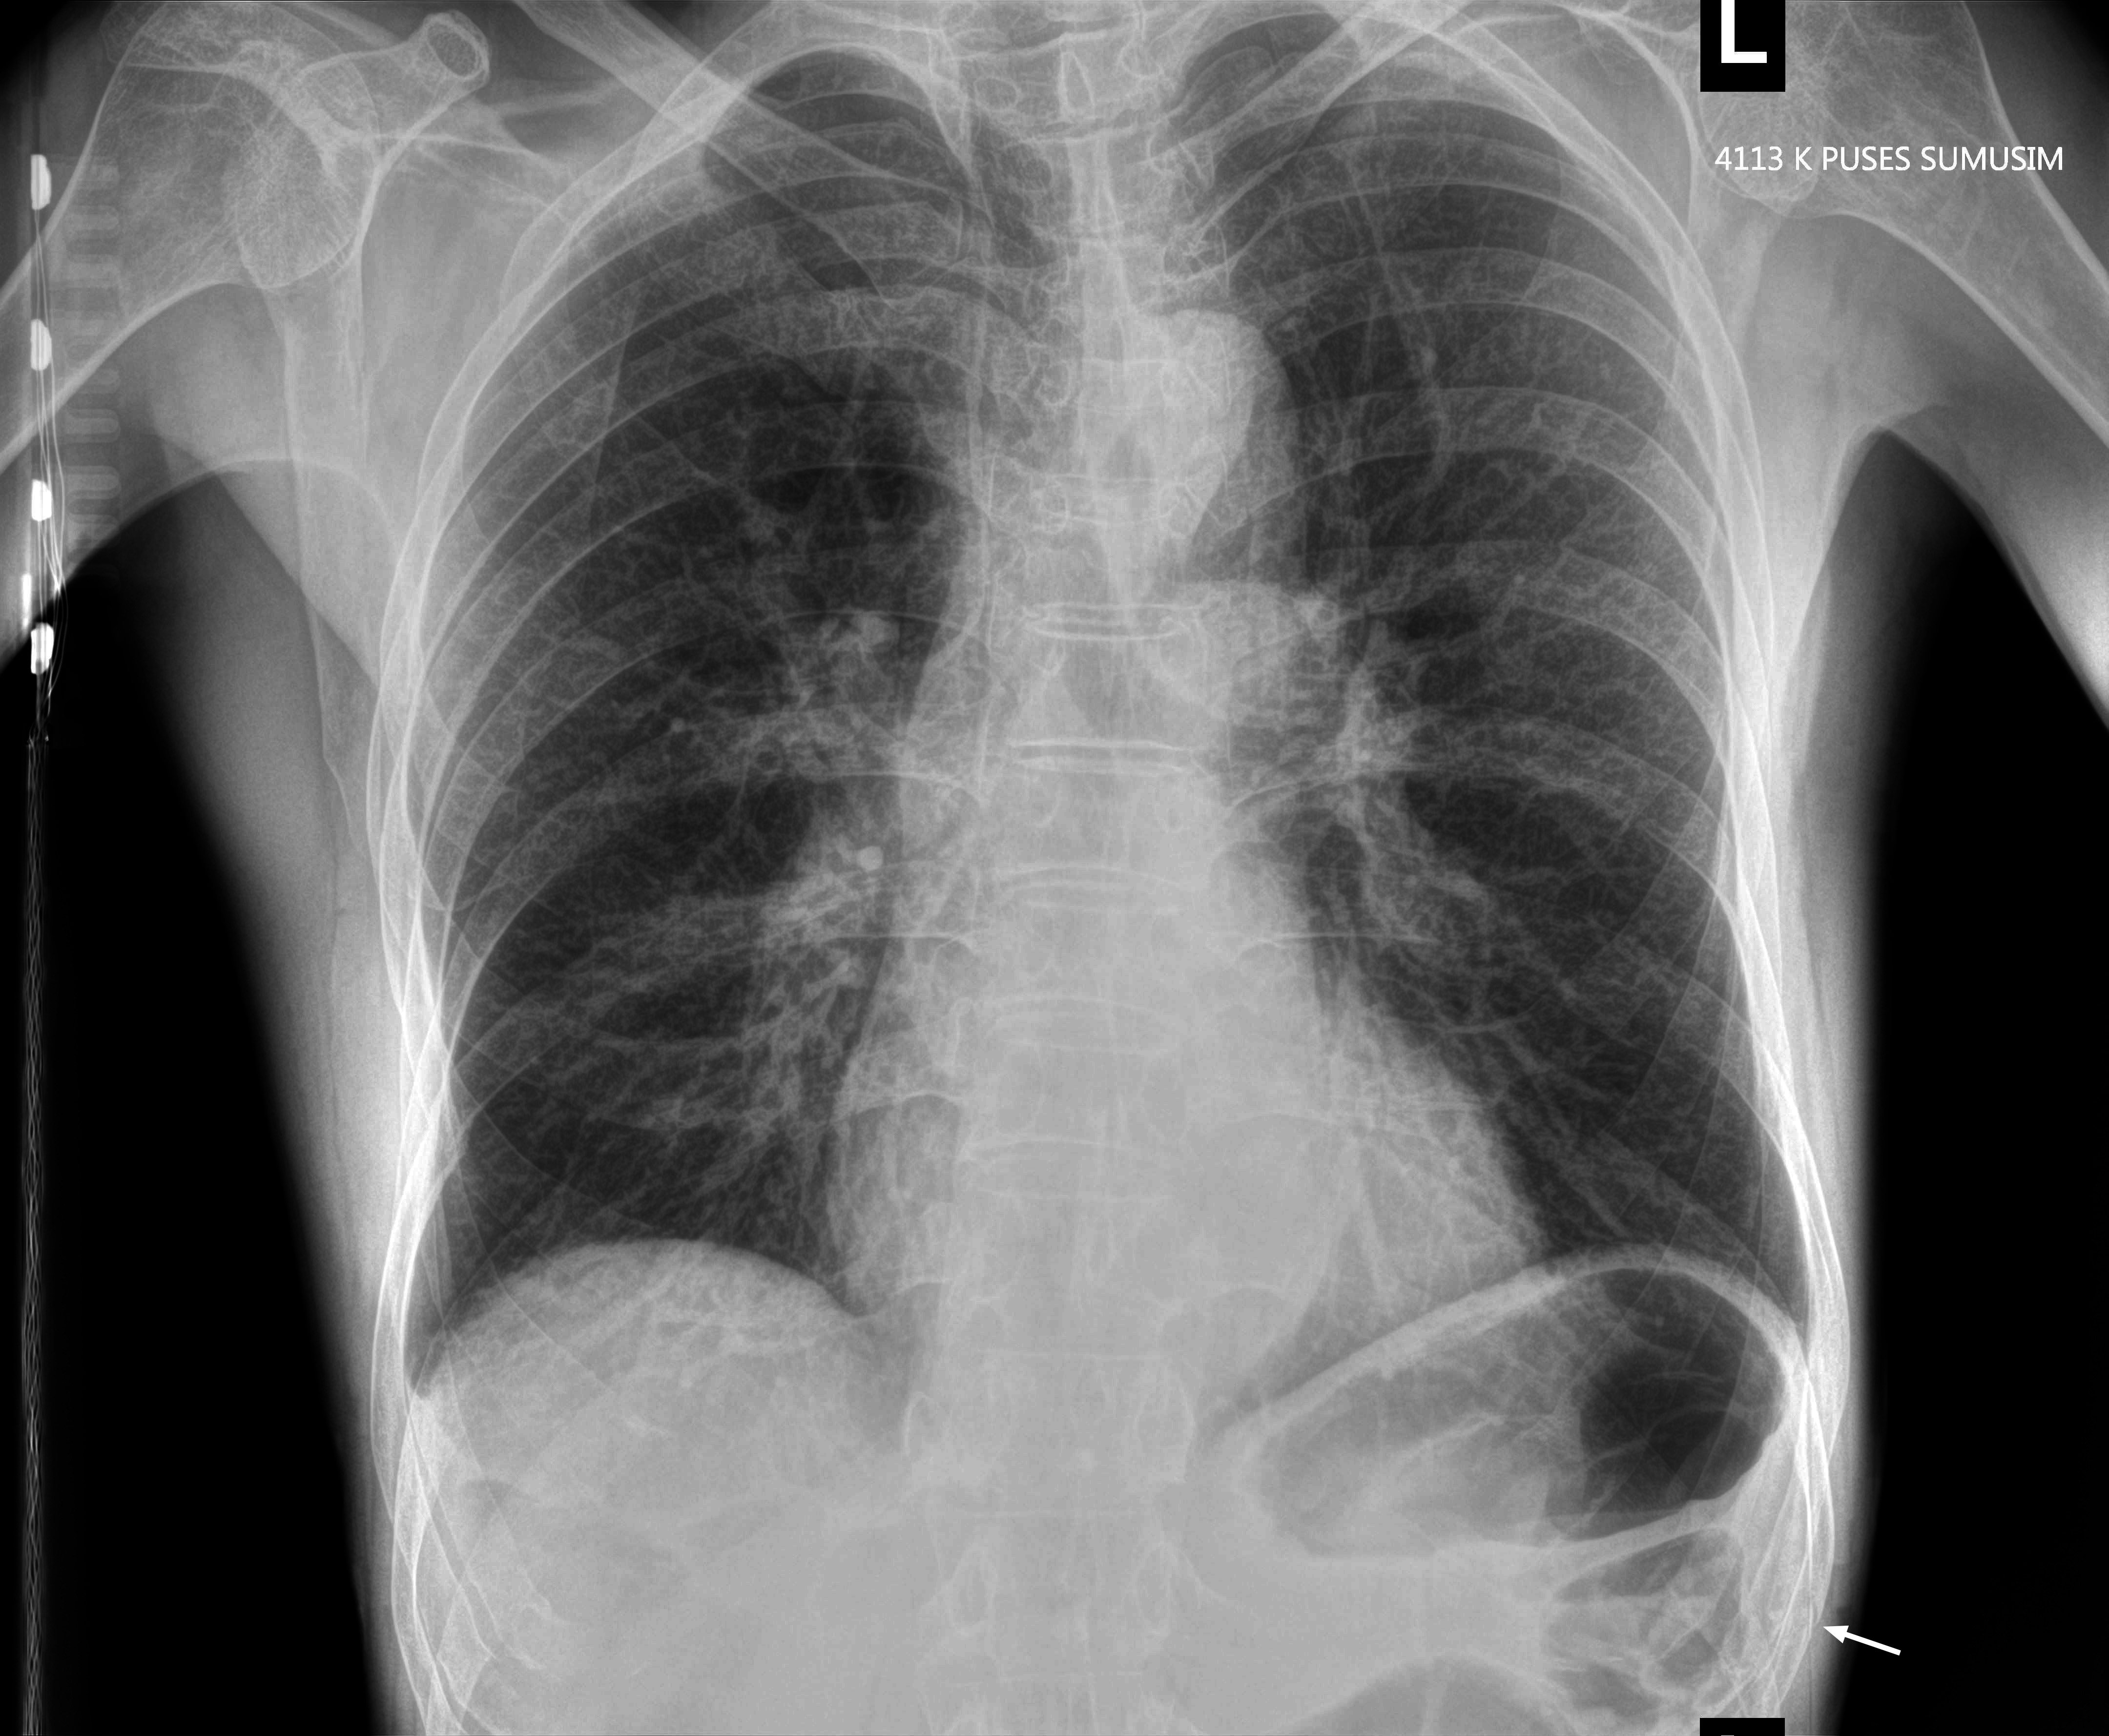

Мужчина средних лет, упал с лестницы 2 недели назад

Свежий (1 день) перелом Х ребра слева.